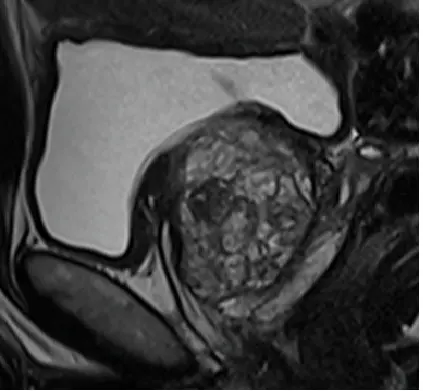

Prostatacarcinom (PIRADS4-Befund)

Diffusionswichtung

Die Untersuchung umfasst verschiedene Bildsequenzen (=multiparametrisch), darunter:

• hochauflösende T2w- Aufnahmen (Beurteilung der Anatomie)

• diffusionsgewichtete Sequenzen (Beurteilung der Zelldichte)

• dynamische Kontrastmittelaufnahmen (Beurteilung der Durchblutung)

Diese Kombination ermöglicht eine sehr genaue Beurteilung nach international anerkannten Kriterien (PIRADS-Befundungsschema).